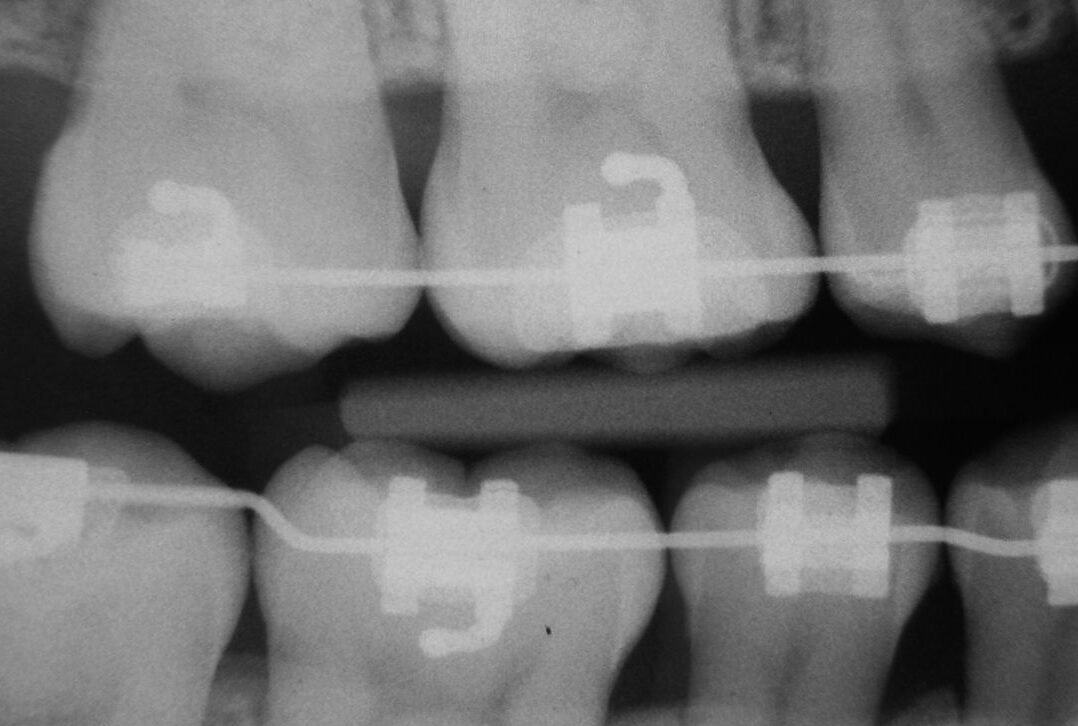

2025.07.23🍽矯正中の食生活で気をつけること|食べてよいもの・避けたいものを解説

2025.07.16🦷部分矯正という選択肢もあります!